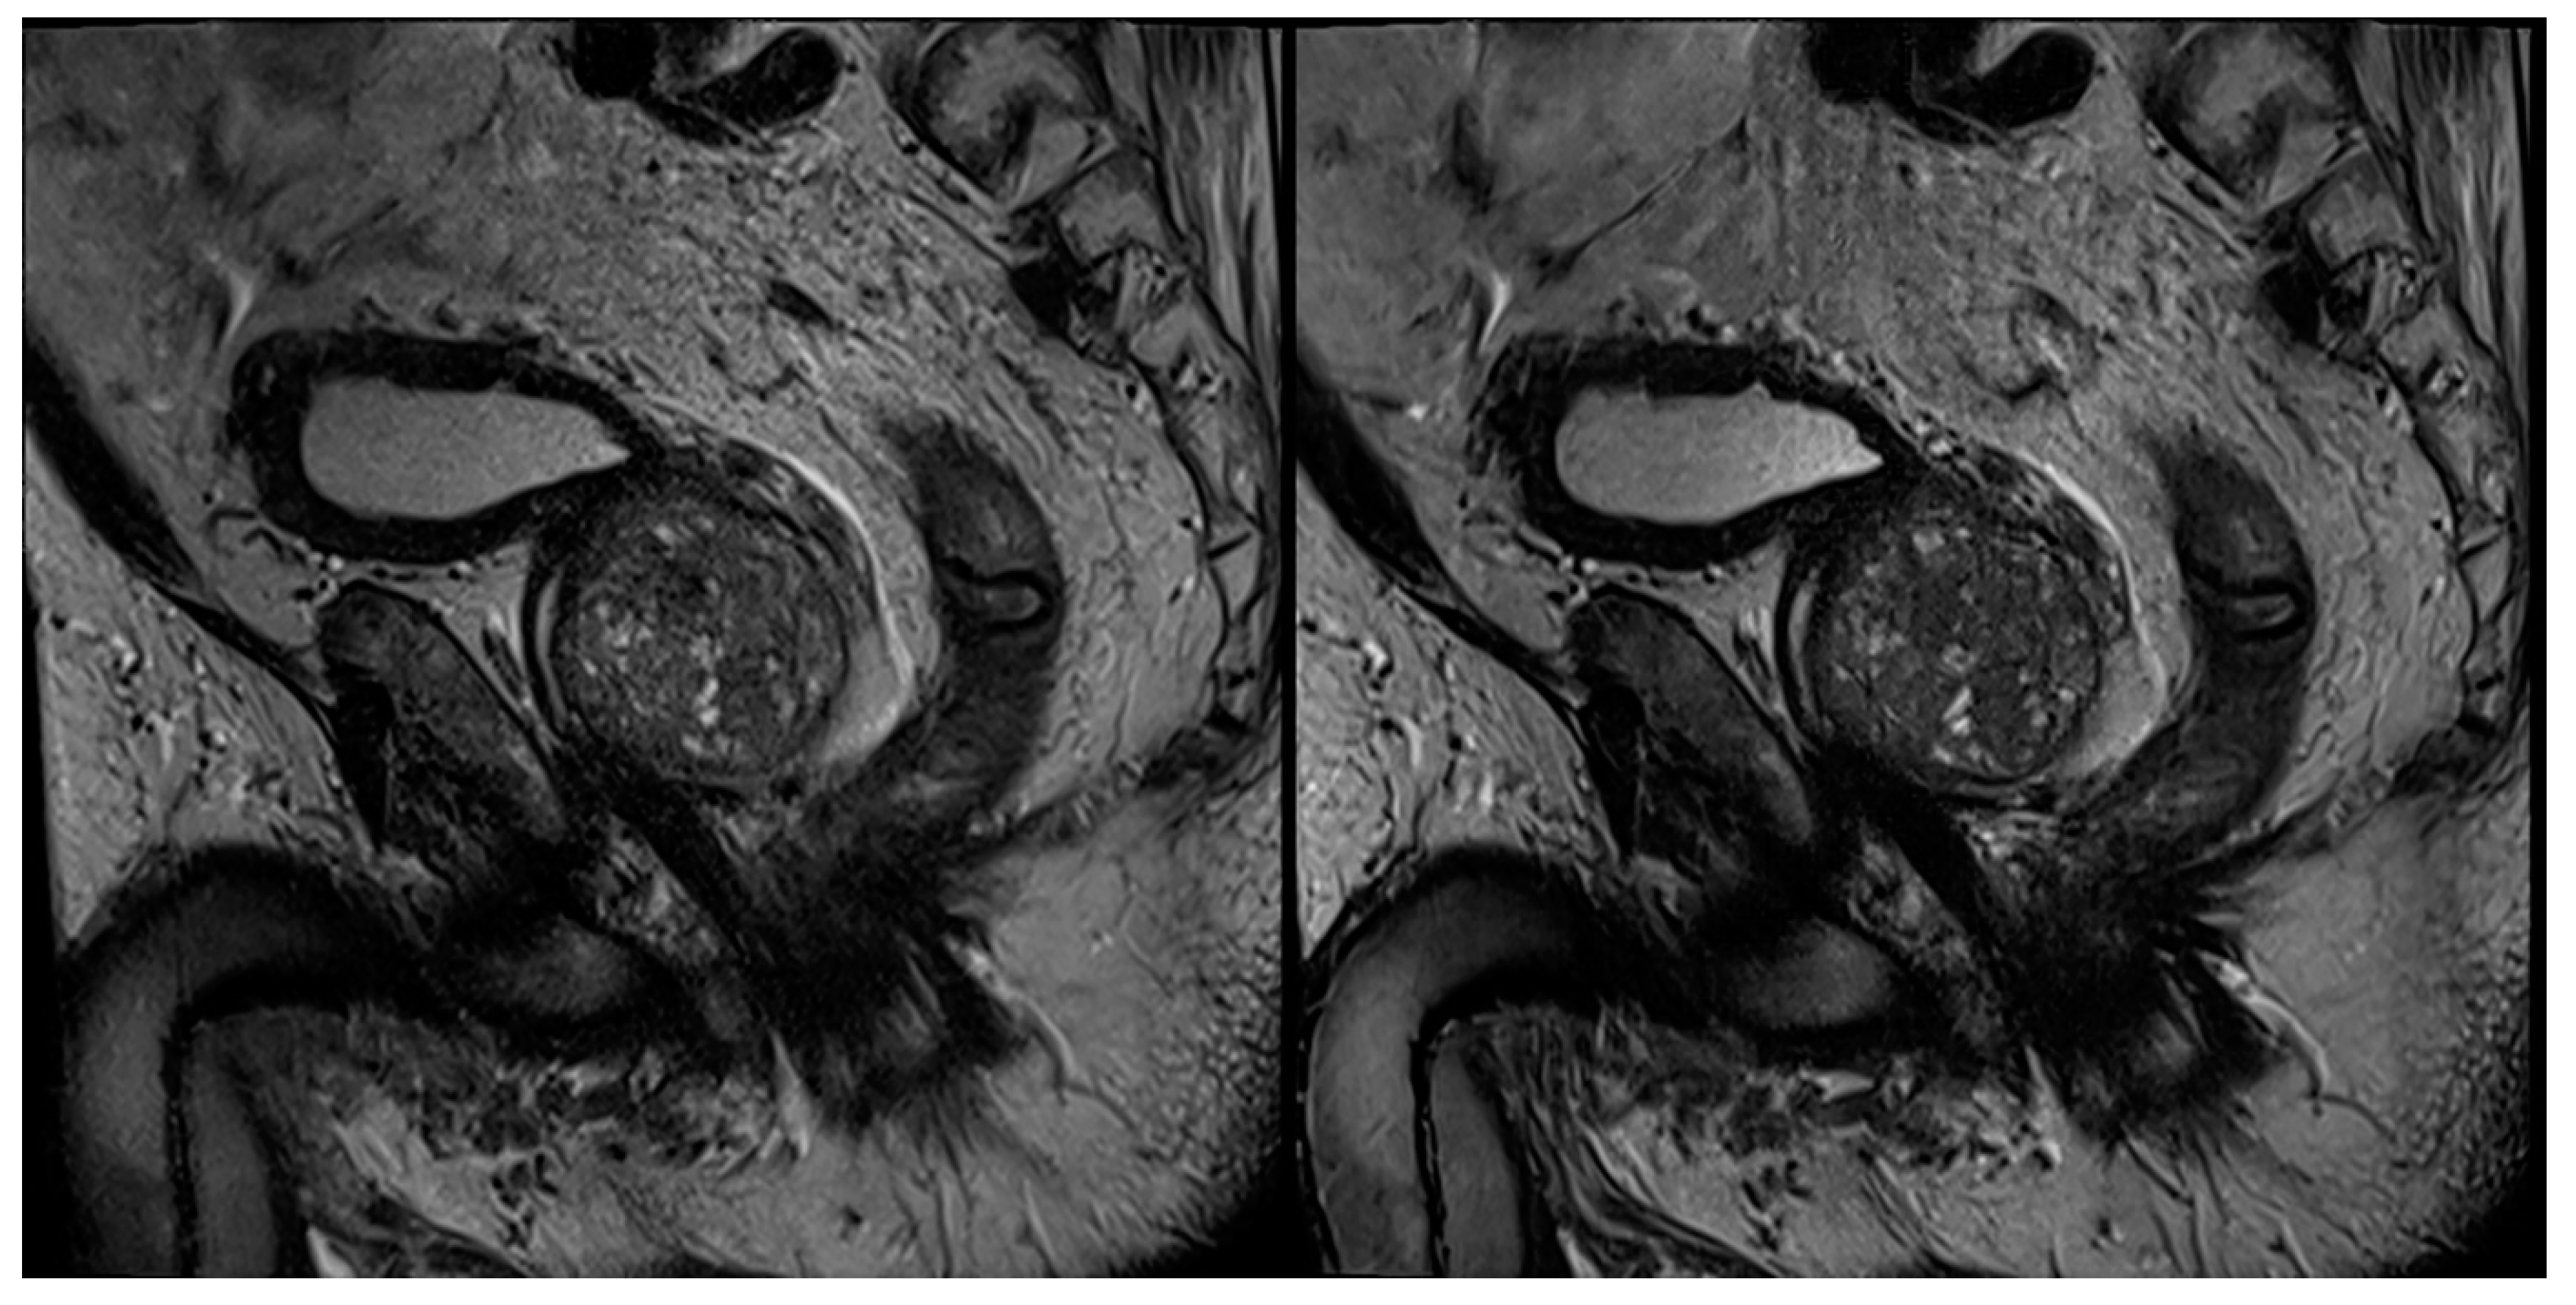

3.3. PI-RADS Scoring and Lesion Conspicuity

4. Discussion

| Lesion size (mm) | 13 (10–16) | 13 (11–16) | 1 | 12 (10–16) | 13 (10–17) | 0.840 |

| Lesion conspicuity | 3 (3–4) | 4 (4–4) | <0.001 | 3 (3–4) | 4 (4–4) | 0.001 |